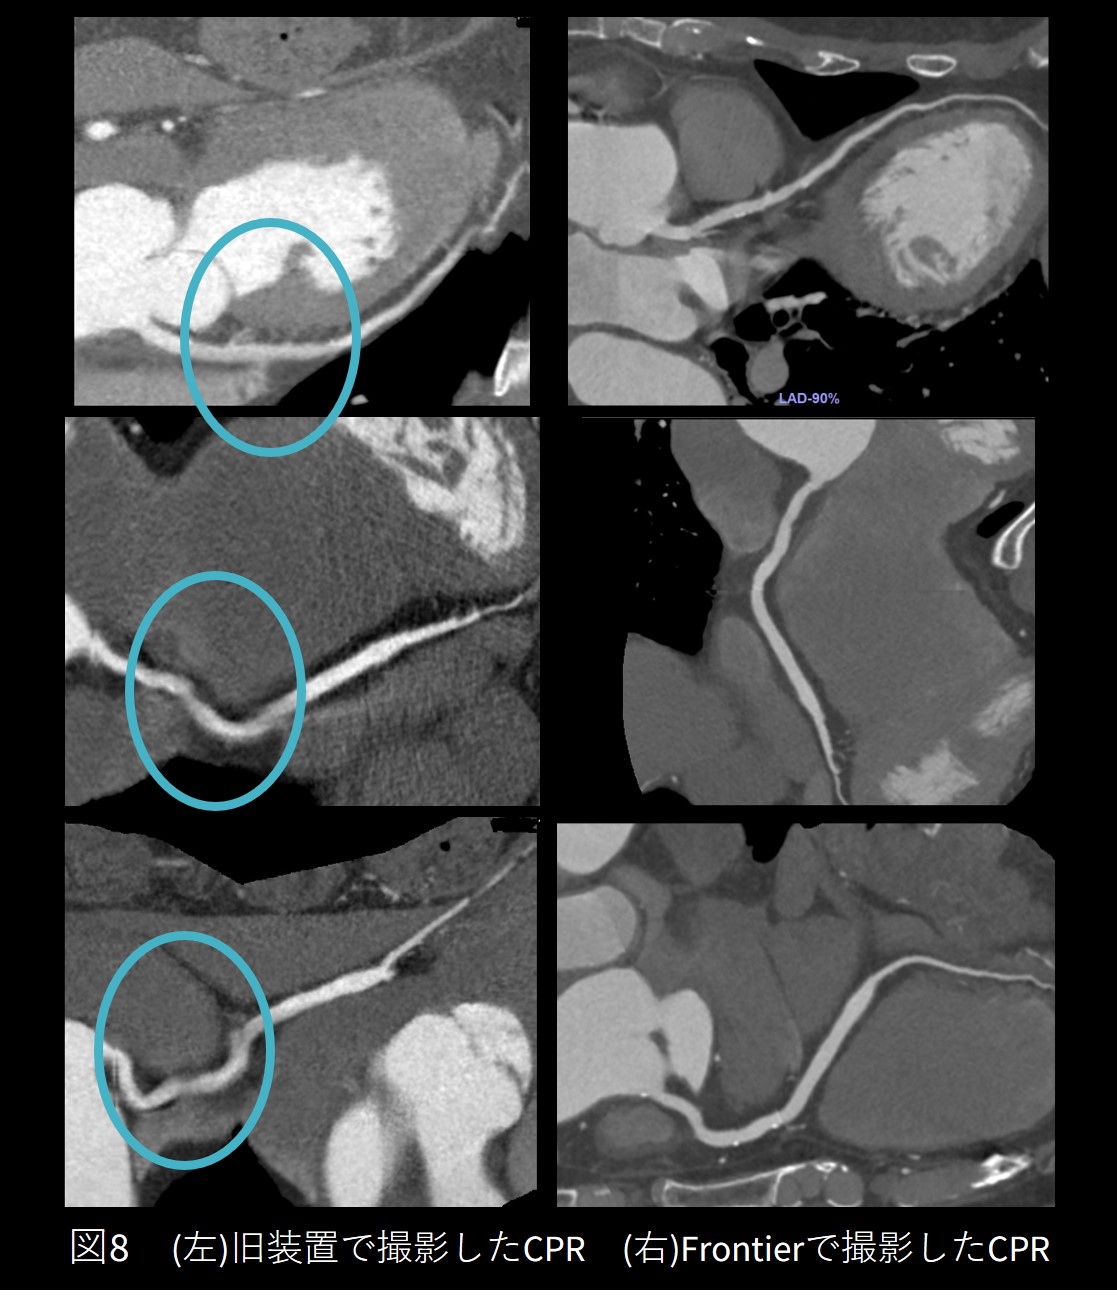

①PMI不整脈症例

徐脈性心房細動にてペースメーカー植え込み術を施行済の症例です。撮影中に不整脈が連続して出現し、すべての不整脈データを削除してしまうと画像を作成することができず、右図の矢印に示すように1心拍を残してSSF2を使用したところ静止画像を得られました。

Frontier_Kofukyoritsu05.jpg

PMIのリードのアーチファクトの影響も少なく、LADの評価が十分にできる画像を構築でき ました。

Frontier_Kofukyoritsu06.jpg